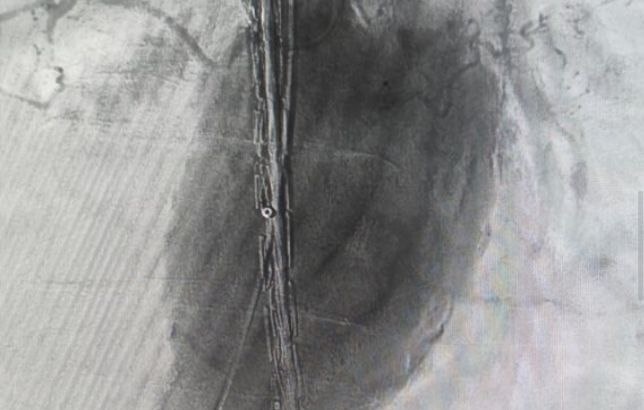

В Волгоградской облбольнице № 1 провели эндоваскулярную операцию пенсионеру с крупной аневризмой. По множеству противопоказаний открытое вмешательство подвергало его жизнь риску.

Фото: комитет здравоохранения Волгоградской области

Специалисты Волгоградской областной больницы № 1 успешно выполнили сложную эндоваскулярную операцию по установке стент-графта для лечения аневризмы брюшной аорты.

Решение о необходимости малотравматичного вмешательства было принято на основе комплекса показаний у пациента: крупный размер аневризмы с высокой угрозой разрыва, симптомы сдавливания органов, а также возраст старше 70 лет и наличие тяжелых хронических заболеваний.

«Стент-графт представляет собой комбинацию стента (металлической или полимерной сетки, которая поддерживает стенку сосуда) и графта (тканевой или синтетической оболочки), который обеспечивает дополнительную прочность и защиту. Конструкция укрепляет стенку аорты изнутри, создавая новый прочный канал для кровотока», – прокомментировали в облздраве.

Таким образом удалось восстановить функцию магистрального сосуда и предотвратить опасные для жизни осложнения.